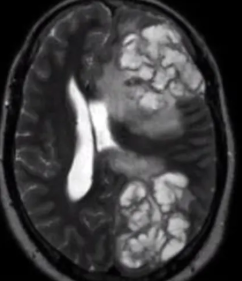

Levadura encapsulada esférica

En qué ayuda la cápsula de polisacáridos de los cryptococos

Inhibe la fagocitosis

Principal factor de patogenicidad del cryptococo

Su cápsula

cápsula, mayor la posibilidad de cruzar la barrera hematoencefálica

• Punción de LCR: Uso de tinta china para ver todo negro y la cápsula color blanco en el microscopio